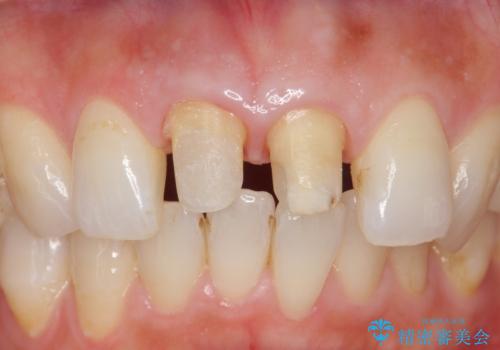

- 前歯の変色を主訴に来院されました。

変色に対してはかぶせ物で周囲の歯との色調を合わせます。

根管治療についてご説明をし、右上の1本だけ再根管治療を行うこととなりました。

先端に透明感のあるかぶせ物を装着することで審美的な問題を解決しつつ、少しガタついていた歯並びも改善することができました。